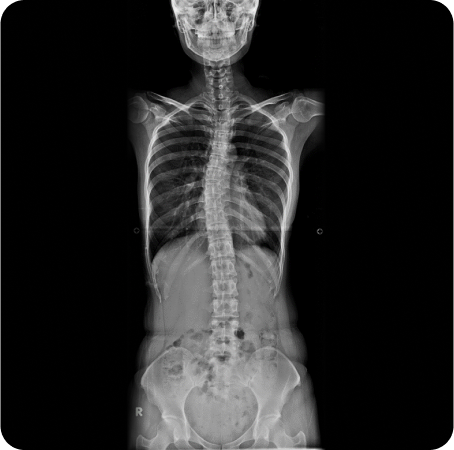

풀스파인 촬영으로

신체의 전체적인 문제를 파악하고

통증의 정확한 원인을 찾아

재발을 예방하고, 통증을 개선하는

치료를 합니다.